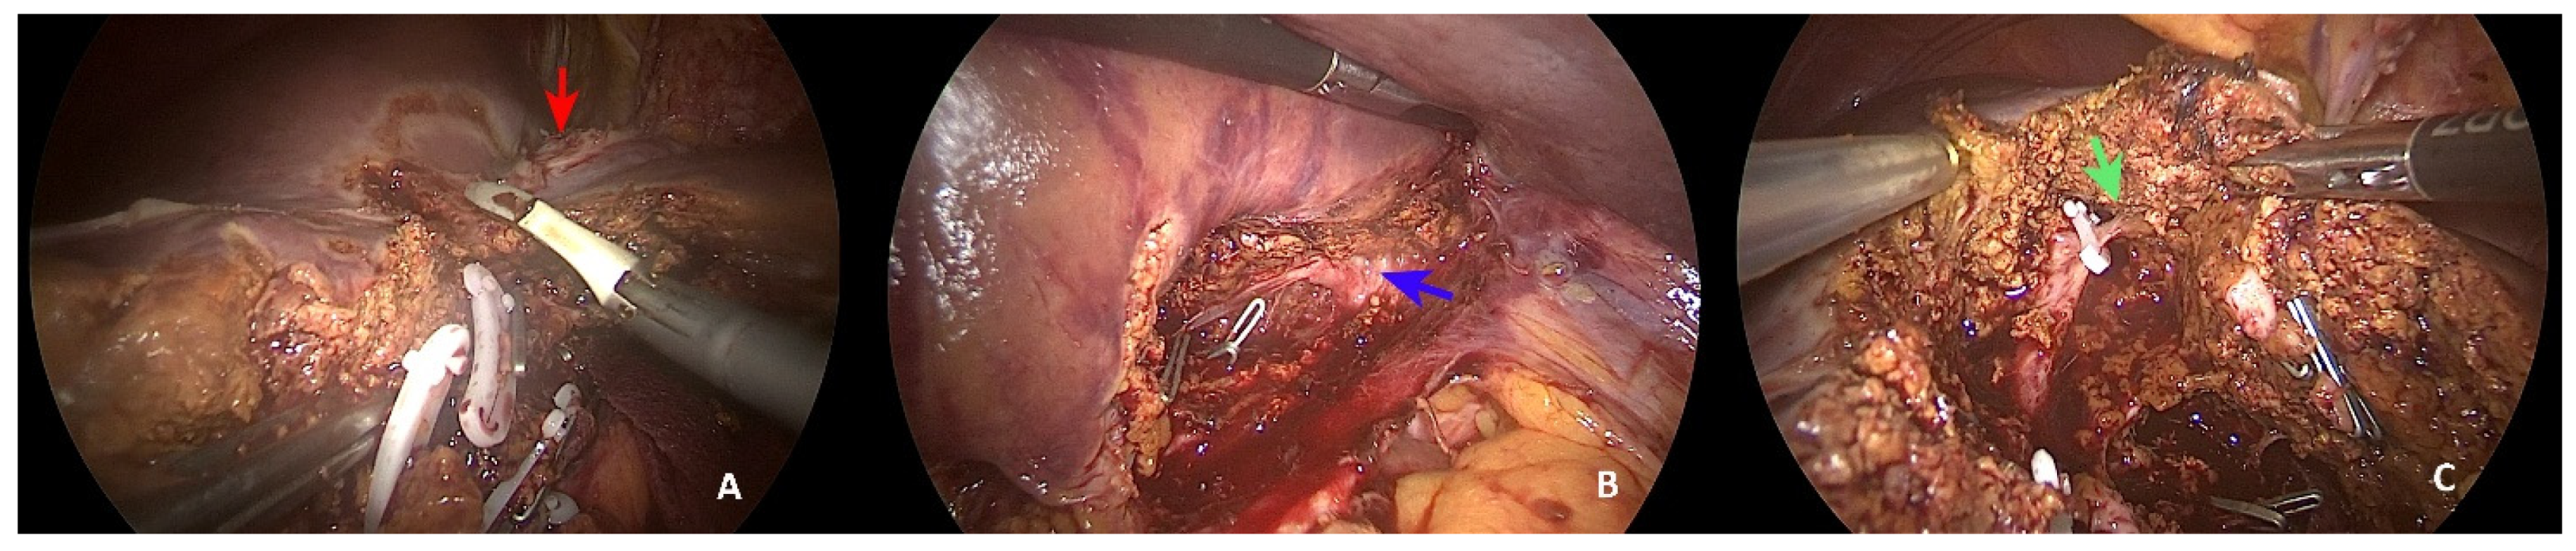

Laparoscopic Resection of Synchronous Liver Metastasis Involving the Left Hepatic Vein and the Common Trunk Bifurcation: A Strategy of Parenchyma-Sparing Resection with Left Sectionectomy and 4a Subsegmentectomy by Arantius Approach

2. Case Presentation